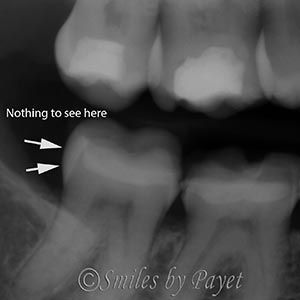

Tooth Cracks Don’t Show Up on X-Rays

One difficulty with diagnosing cracks in teeth, is that they almost never show up on x-rays. Why, you ask? Good question! It’s because x-rays are traveling perpendicular to the cracks, and the cracks are so narrow, there’s not enough change in the tooth density for the x-rays to show it. To show up on an x-ray, a crack in a tooth would have to be so wide, you could stick a fork in it, and then you’d already know there was a problem. The x-ray shown here is from another patient we recently treated, and while you can’t see anything on the x-ray, want until you see how it looked inside the tooth (on below).